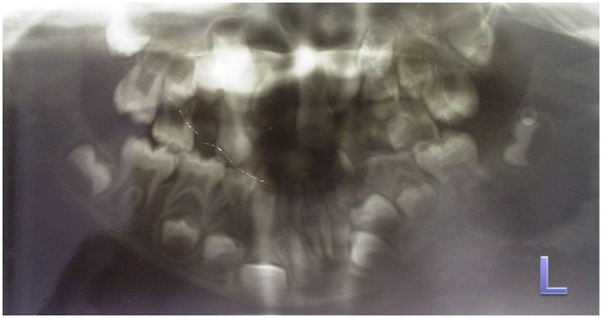

A 6 year old male patient, born of non consanguineous marriage, presented to our department with the complaint of deformed left ear since birth. It was associated with decreased hearing. Medical history revealed cleft palate surgery at the age of 1 year. The child was born of a full-term normal delivery and there was no history of any maternal illness during the pregnancy. But the child was cyanotic at the time of birth. All other family members were normal. Personal history showed normal bowel and bladder habits, undisturbed sleep. On General Examination, he was conscious and cooperative but had reduced grasping power and learning skills. Vital signs were within normal limits with no peripheral signs. Altered posture was noticed as the shoulder levels were not at same level (Figure 1). On extra oral examination, facial asymmetry was detected due to hallowing of left cheek and hypoplasia of left malar region, hypoplasia of maxillary bone and prognathic mandible (Figure 2). Facial profile was straight and leptoprosopic facial form was noticed. Deformed left ear and ear tags were seen on the right side (Figure 3). Hypertelorism was present. Ocular changes showed whitish area near outer canthus of both eyes approximately measuring 1X1cms suggestive of epibulbar dermoids on both sides (Figure 4). Cranial nerve examination revealed left facial nerve paralysis as he was unable to raise his eyebrows, no wrinkles on the forehead and unable to blow the cheeks on left side. On Intraoral Examination, palatal scar noticed suggestive of previous surgery for cleft palate and hard tissue examinations showed multiple root stumps and Angle’s class III malocclusion. The orthopantomograph showed mixed dentition (Figure 5) and the lateral cephalograph revealed malar and maxillary hypoplasia (Figure 6). We diagnosed the patient as a case of Goldenhar syndrome on the basis of multiple accessory tragi, ocular dermoids, hypoplastic malar process, facial nerve paralysis, mental retardation and skeletal abnormalities. Patient was referred for auricular surgery followed by ear prosthesis replacement.

Figure 5 Orthopantamograph showing mixed dentition.